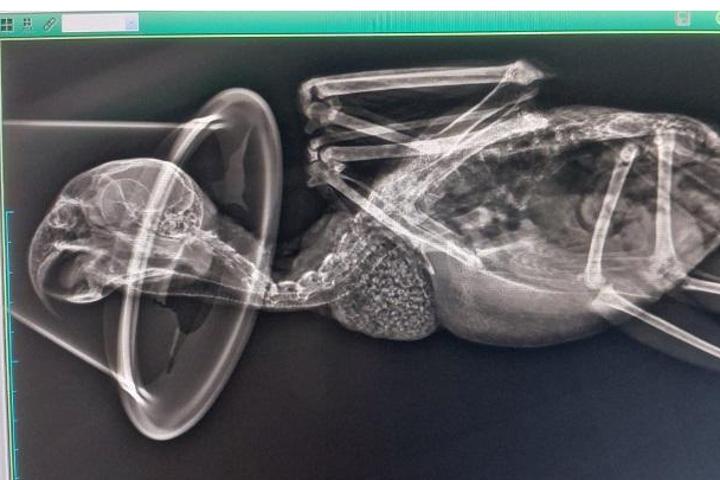

Abrimos este Teaming exclusivamente para ayudar a costear gastos veterinarios. Cada vez son más las aves que tenemos a nuestro cargo y los gastos se van sumando; revisiones a las nuevas entradas, analíticas, revisiones anuales, medicación...Más las urgencias. Cada euro cuenta y vuestra ayuda es fundamental para poder dar una vida digna a las aves a nuestro cargo. Muchas gracias por vuestro apoyo.

Destinamos la recaudación a los gastos veterinarios de la protectora, que son muchos, puesto que a las revisiones, analíticas y seguimiento de los residentes se suman los tests de enfermedades y pruebas a las nuevas entradas, sin contar con las urgencias... Con vuestra ayuda, cubriremos aunque sea una mínima parte de todos estos gastos. Gracias por estar ahí.

Estamos teniendo una entrada masiva de aves abandonadas en nuestro centro.

No paramos de recoger aves heridas.